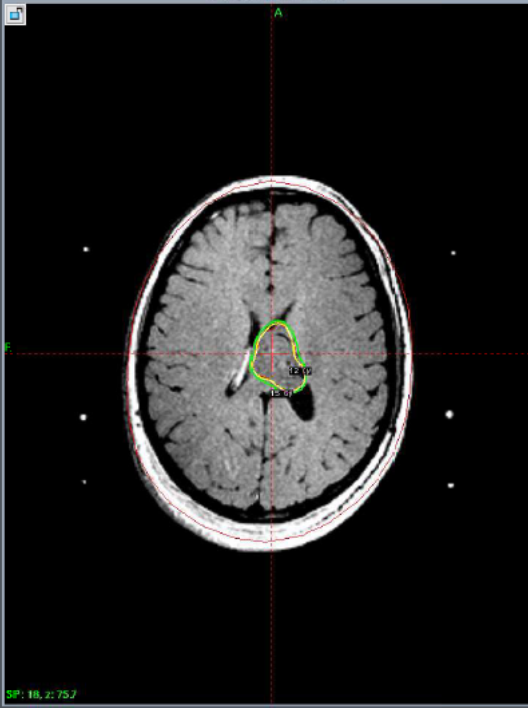

Ependymoma, Two years follow up.

17 yrs, Female.

with persistent headache.

MRI showed

non enhancing mass

periventricular area

more on Lt. side.

Burhole biopsy

showed

Ependymoma Gr.II.

Complete resolution after one year of Gamma knife Treatment.

At GKRS                             After one year                              After Two years